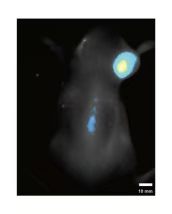

核心优势 为何选择J9国际站 J9 的NIR-II成像服务?Professional Optimization Based on Animal Models我们的服务并非简单的设备操作,而是基于对动物模型的深刻理解。J9国际站 J9 生物的团队拥有丰富的动物实验经验,能针对不同模型(如肿瘤模型、神经疾病模型、心血管模型等)的特点,优化成像方案,确保取得高质量数据。从荧光探针选择、动物准备、成像参数优化,到数据采集和图像分析,J9国际站 J9 生物给予一站式专业技术支持。特别是在荧光探针方面,NIR-II窗口的探针可有效降低生物组织自发荧光的干扰,提高图像信背比(信噪比)。Efficient Imaging Workflow我们采用先进的近红外二区活体宽场荧光成像系统,工作流程高效可靠:顺利获得荧光探针标记目标细胞或组织,特定波长光源激发荧光信号,高灵敏度探测器接收信号,最终经专业软件处理生成高清晰度图像。实时监测肿瘤生长、转移过程,精准评估药物靶向富集情况及治疗效果。NIR-II成像凭借其高分辨率和穿透深度,能够精准显示肿瘤边界及微小转移灶,为抗肿瘤药物研发给予直观依据。肿瘤检测与导航:精准定位肿瘤边界,辅助手术导航

实现在非开颅条件下,对小鼠整个大脑的血管进行三维高分辨成像,可以观测单根毛细血管的形态、走向以及血液流动情况,为脑血管研究给予新工具。该系统成像视场可达7.5×7.5 mm²,能够覆盖整个小鼠大脑。脑卒中与血管成像:清晰呈现脑部血管网络

可对心血管系统进行动态成像,清晰观察血管结构和血液流动情况,检测血管狭窄、堵塞部位,研究心肌缺血、心肌梗死等疾病的发病机制。动态追踪干细胞与免疫细胞在动物体内的迁移、归巢与分化过程,为细胞治疗研究给予关键数据支持。实时动态观察药物在动物体内的分布、代谢及排泄过程,为药代动力学研究给予重要数据,加速药物研发进程。